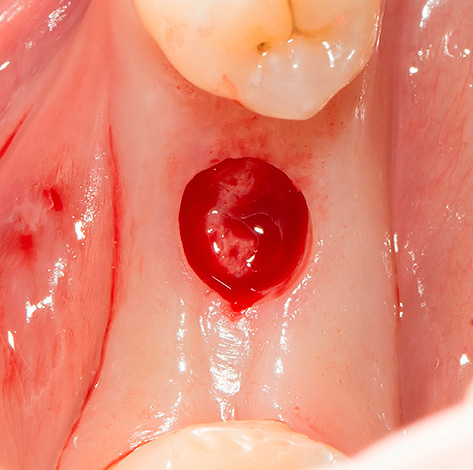

É importante entender que os dentistas costumam usar o termo “implante rápido” (e similares do segundo grupo) para caracterizar o processo de instalação de implantes dentários em uma consulta - geralmente imediatamente após a extração do dente. Ou seja, nesse caso, você não precisa cortar nada, porque uma ferida aberta se abre na gengiva após a extração do dente doente, pronta (embora nem sempre) para instalar o implante com o modelador de goma fixo.

Antes de falar sobre as muitas vantagens do implante imediato, lembramos mais uma vez que esse processo é chamado não cirúrgico, como se costuma dizer, “a linguagem não muda”. E sim, pode não haver uma incisão gengival, uma vez que não é necessária, porque um novo orifício em um dente que acabou de ser removido muitas vezes já é adequado para a colocação do implante sem manipulações adicionais com um bisturi.

- No caso de implante simultâneo, a extração dentária, a instalação de um implante e um formador de goma são realizadas em uma visita à clínica;

- Um corte circular é realizado ("punção");